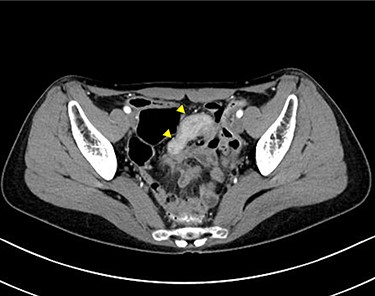

A 45-year-old woman was admitted with recurrent abdominal pain. She had no significant past medical history. Physical examination showed mild tenderness in the lower abdomen. Laboratory findings were within normal limits, except for serum carbohydrate antigen 19-9 (58 U/mL). Computed tomography (CT) scan showed a continuous lesion to the ileum with contrast enhancement (Fig. 1). Retrograde double-ballon enteroscopy showed an ulcerated lesion at 160 centimeters from the ileocecal valve, and biopsy showed well-differentiated adenocarcinoma (Fig. 2). An enteroscopy-assisted contrast study revealed intestinal stenosis involving a Meckel’s diverticulum (Fig. 3). Based on these findings, we diagnosed adenocarcinoma in a Meckel’s diverticulum preoperatively. Intestinal resection with lymph node dissection was performed. Operative findings showed that the tumor invaded the Meckel’s diverticulum 160 centimeters from the ileocecal valve. No findings of abdominal dissemination were observed (Fig. 4). Histological examination of the resected specimen revealed a well-differentiated adenocarcinoma, interrupted by ectopic gastric mucosa (one side shown, Fig. 5a.).

Computed tomographic scan showing a continuous lesion to the ileum with contrast enhancement (arrowheads).

(a) Computed tomography scan showing a multi-cystic mass in the pelvis with a partial contrast effect. (b) Gadolinium-enhanced T2-weighted magnetic resonance image showing a solid mass with contrast effect in the cysts.